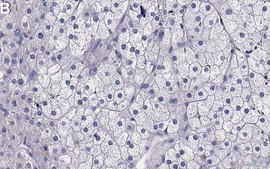

Immunohistochemistry (Paraffin) Analysis: A 1:100 dilution from a representative lot detected TrkA in human adrenal gland tissue sections.